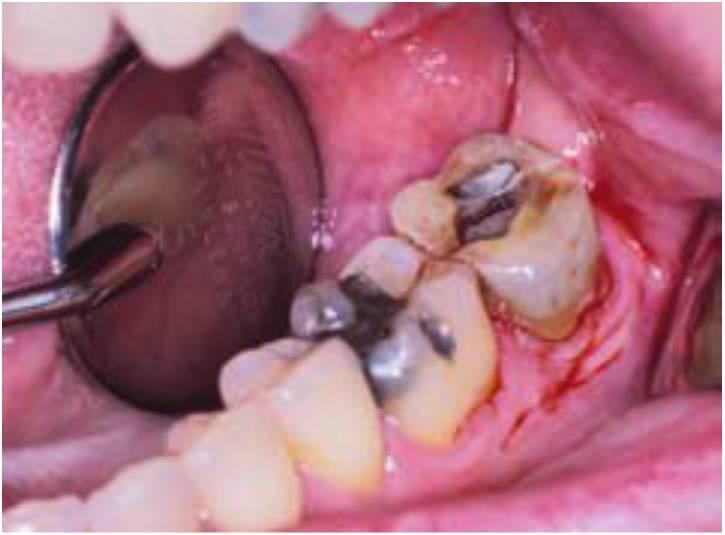

Este patrón de engranaje normalmente continúa después del tratamiento. Si el dentista restaurador restablece la guía incisiva sobre los dientes que se han visto gravemente afectados por el patrón de engranaje bruxista, se aumentará la incidencia de complicaciones sobre esos dientes. Las complicaciones más frecuentes sobre los dientes restaurados con este «método de destrucción» son la fractura de la porcelana, descementación de prótesis y fractura radicular. Cuando los implantes soportan las coronas en el marco de esta senda de destrucción, el implante podrá fracasar, fracturarse o presentar una pérdida de hueso crestal, asimismo se puede perder el to millo del pilar, fracturar la porcelana o desprenderse las restauraciones. Si el paciente continúa con un patrón grave de bruxismo, la pregunta no sería si aparecerán complicaciones, sino cuándo y cuáles. El dentista debe avisar al paciente de que estos hábitos causan esos problemas. El tratamiento puede estar enfocado a reparar estos problemas, pero existirán complicaciones si no se reduce el bruxismo.

El apretamiento aumenta el riesgo de fallo mecánico, como fractura de la porcelana, descementación de restauraciones, fractura del tornillo del pilar, fractura del cuerpo del implante y pérdida de hueso crestal (fig. 6-18).